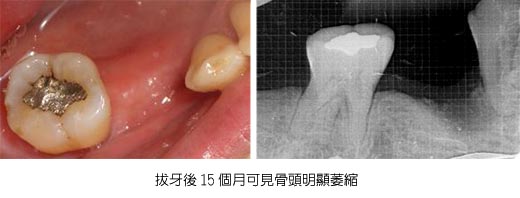

20100811植牙與補骨~龍霖醫師

2010-08-11